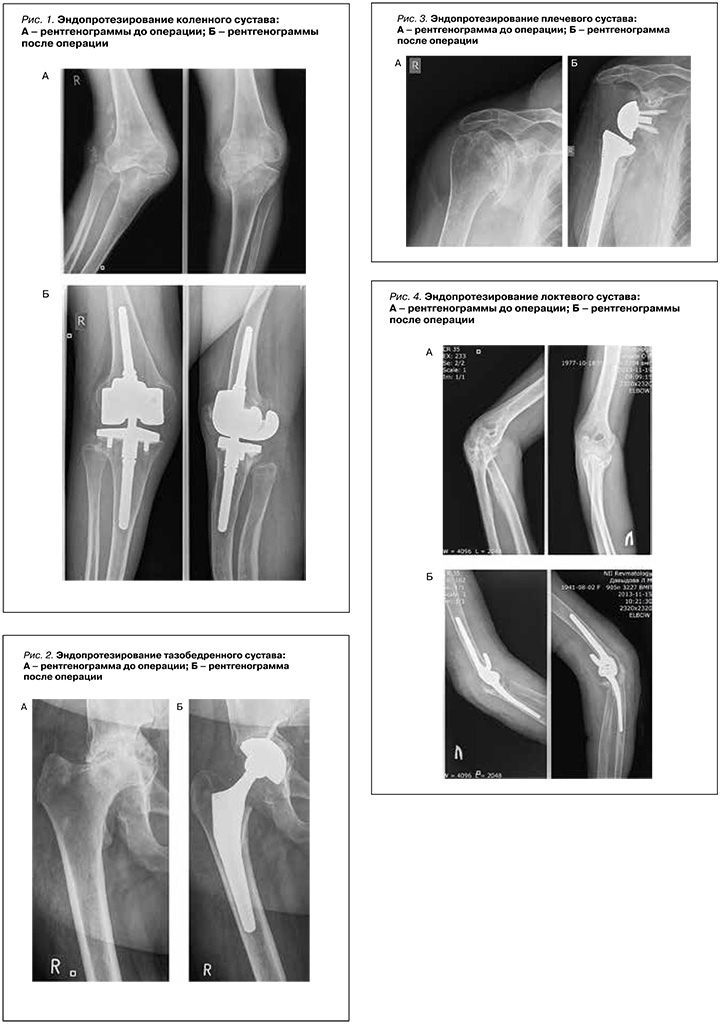

Популяризация эндопротезирования связана с именем сэра Джона Чанли. Именно он внедрил в практику трибологические принципы современного эндопротезирования. Они состояли в использовании шарнирного соединения металлической полированной поверхности и полиэтиленового вкладыша высокой плотности. Компоненты эндопротеза фиксировались в кости с помощью полиметилметакрилата (костного цемента) [39]. Сегодня проведение этой операции на тазобедренном и коленных суставах – рутинная ортопедическая практика (рис. 1, 2; фотографии публикуются с согласия пациентов), при этом 10-летняя выживаемость пациентов после нее достигает рекордных 90%, несмотря на наличие системного аутоиммунного заболевания [40].

Результаты эндопротезирования плечевого и локтевого суставов в настоящее время можно считать удовлетворительными, а 10-летняя выживаемость после таких вмешательств составляет 80 и 70% соответственно (рис. 3, 4).